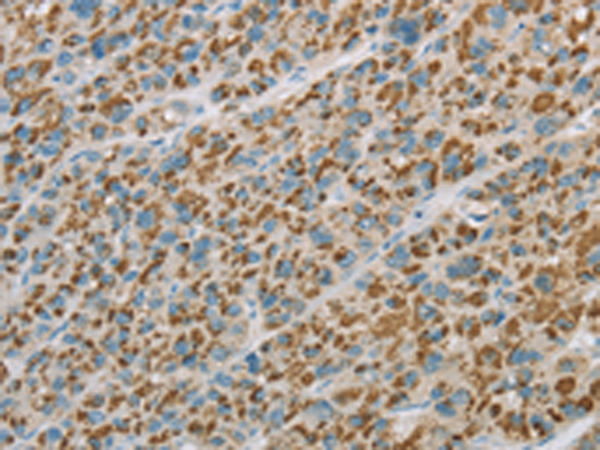

分类: 科研抗体货号: P08288别名:应用: IHC反应种属: Human, Mouse